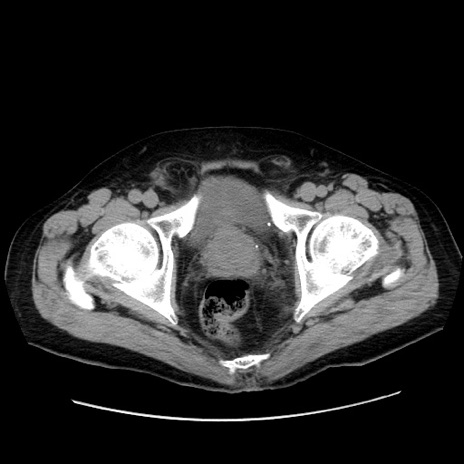

症例30(横断像)

【症例】80歳代男性

【主訴】臍周囲痛

【現病歴】約6時間前から臍下部痛が出現。次第に腹部膨隆・背部痛も生じてきたため来院。背部痛の場所は変化しない。

【既往歴】腎盂腎炎

【身体所見】意識清明、BT 36.3℃、BP  131/87mmHg、P 87bpm、SpO2 100%(RA)、臍周囲自発痛・圧痛あり、反跳痛なし、自発痛部位に一致して板状硬あり、腹部膨隆、腸雑音減弱、CVA tenderness両側陰性。

【データ】WBC 19600、CRP 0.33